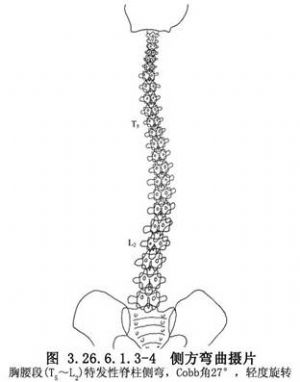

脊柱側彎是指脊柱的側方彎曲畸形。脊柱側彎按其病因可分爲繼發性、非進行性、非結構性脊柱側彎和原發性、進行性、結構性脊柱側彎兩種。前者是由於脊柱以外的異常而引起的脊柱側彎,如姿勢性脊柱側彎;而後者則由於脊柱發生內在的椎體及其支持結構的改變所引起,如特發性脊柱側彎。結構性脊柱側彎向兩側彎曲的曲線常不對稱,而非結構性脊柱側彎多爲對稱(圖3.26.6.1.3-0-1~3.26.6.1.3-0-3)。

特發性脊柱側彎爲側彎前凸畸形,臨牀上約佔脊柱側彎總數的75%~85%。此處只限介紹特發性脊柱側彎的手術治療。

(1)攝立位脊柱全長正側位相,以測量脊柱側彎度、旋轉度,並對脊柱側彎進行正確分類及分型。爲了解脊柱是否伴有前凸或後凸,應攝側彎頂角椎體的正側位相。

(2)攝臥位雙側彎曲脊柱正位相或懸吊位相。其意義是:瞭解脊柱側彎是結構性或是非結構性;了解結構性側彎(原發性側彎)的範圍,以確定脊柱融合的椎體範圍;瞭解畸形脊柱的彈性,估計術中器械矯形可達角度。向側彎凸側彎曲時結構性側彎的角度改變,大約與術中器械矯形可達到的角度一致(圖3.26.6.1.3-4~3.26.6.1.3-6)。